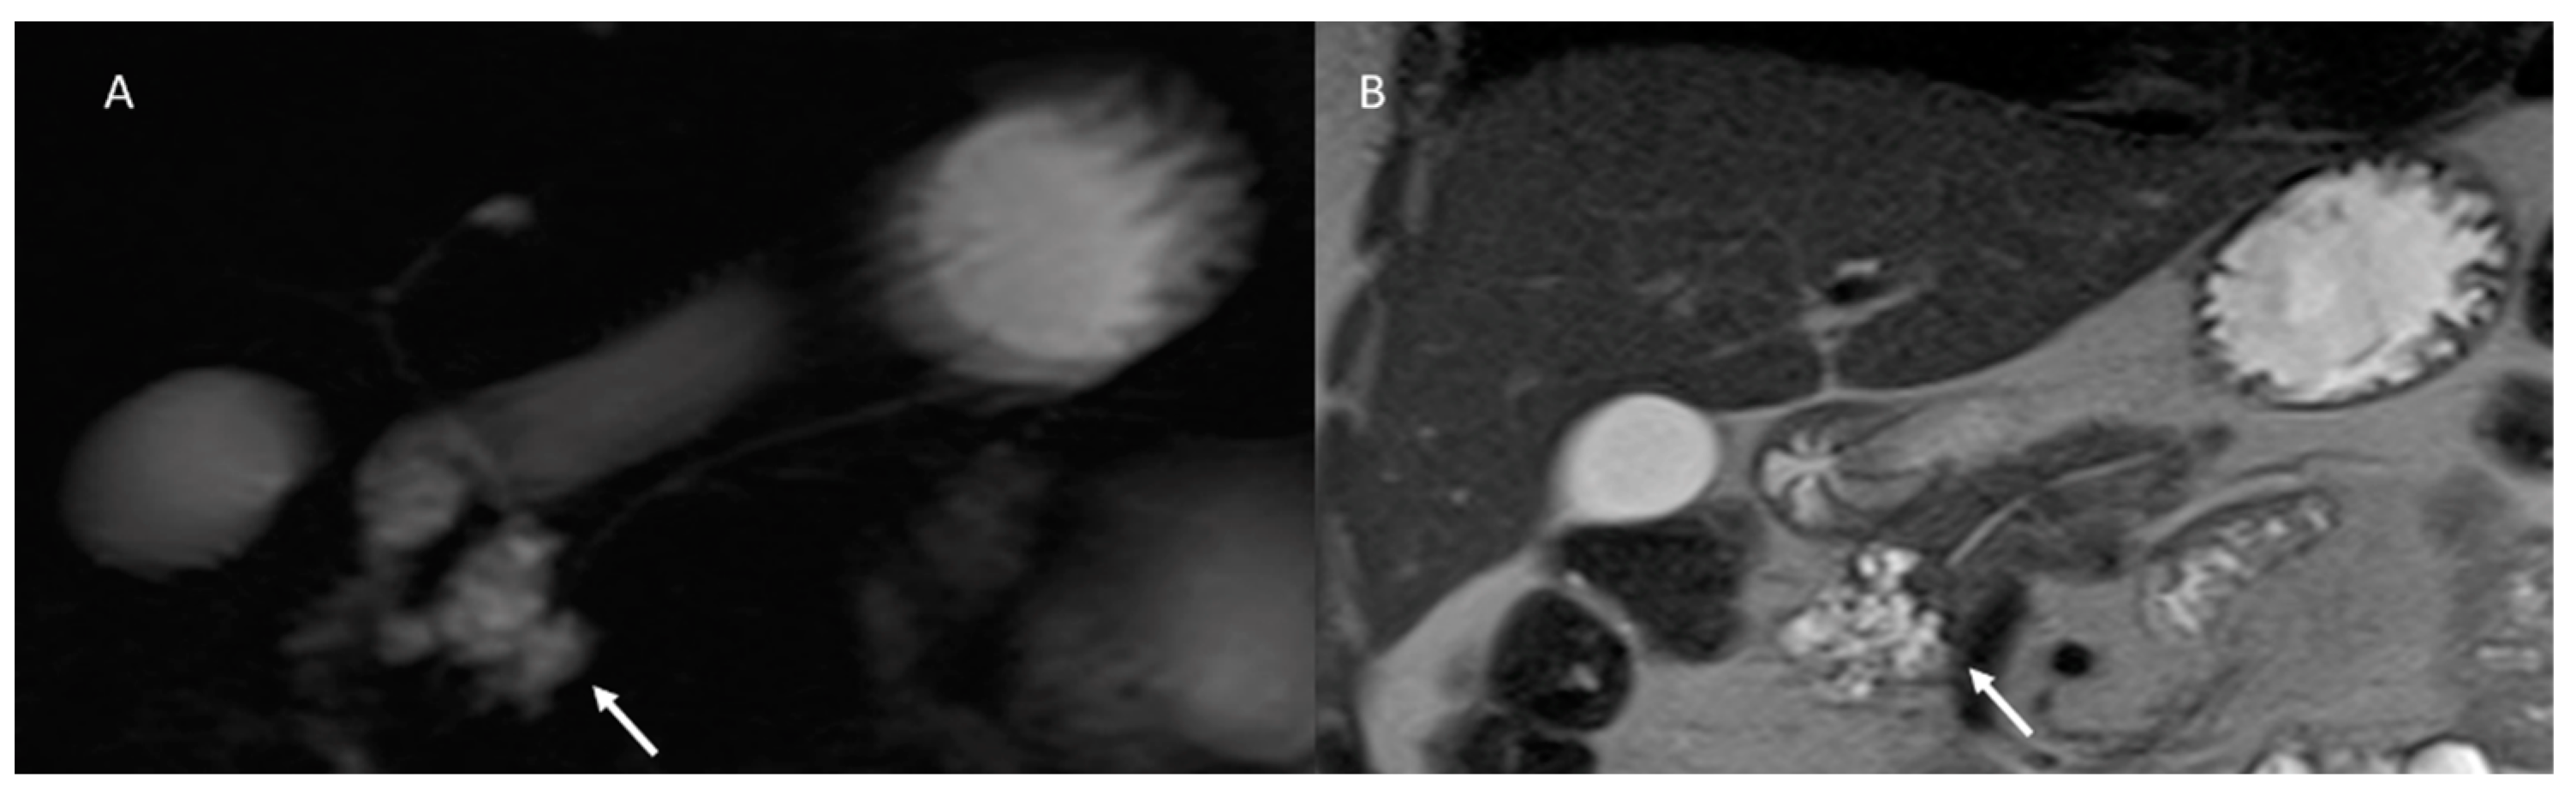

- Girometti, R.; Intini, S.; Brondani, G.; Como, G.; Londero, F.; Bresadola, F.; Zuiani, C.; Bazzocchi, M. Incidental pancreatic cysts on 3D turbo spin echo magnetic resonance cholangiopan-creatography: Prevalence and relation with clinical and imaging features. Abdom. Imaging 2011, 36, 196–205. [Google Scholar] [CrossRef]

- Sahani, D.V.; Kambadakone, A.; Macari, M.; Takahashi, N.; Chari, S.; Castillo, C.F.-D. Diagnosis and Management of Cystic Pancreatic Lesions. Am. J. Roentgenol. 2013, 200, 343–354. [Google Scholar] [CrossRef] [PubMed]